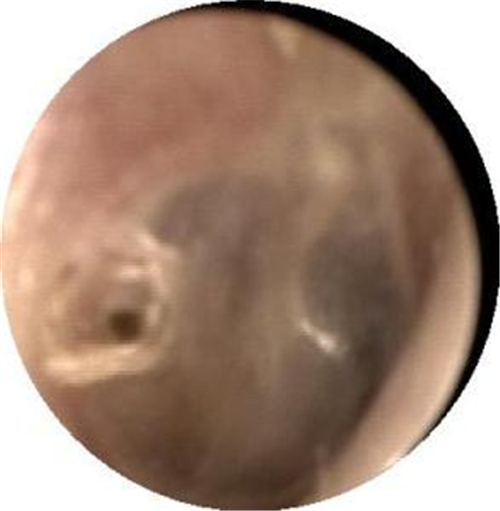

左耳鼓膜穿孔